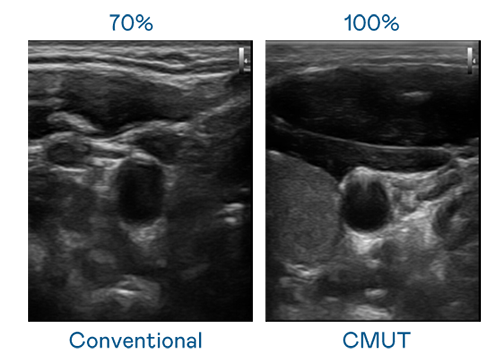

CMUT 技术是一种用电容式微机电元件来产生超音波讯号的技术。与传统 PZT 压电式技术相比,CMUT 频宽增加 30%,更宽频的超音波讯号让影像解析度大幅提升,是实现高影像品质医疗超音波扫描、促进精准医疗发展的关键技术。

大频宽带来超清晰影像

超音波影像的解析度高低,首先取决于探头能发出的讯号频宽。AG百家乐官网 CMUT 可提供高清晰的超音波讯号,提供高频宽、高灵敏度、影像纹理细节更高的超音波影像,协助医护人员缩短影像判读时间及利用精准的医疗影像进行诊断。